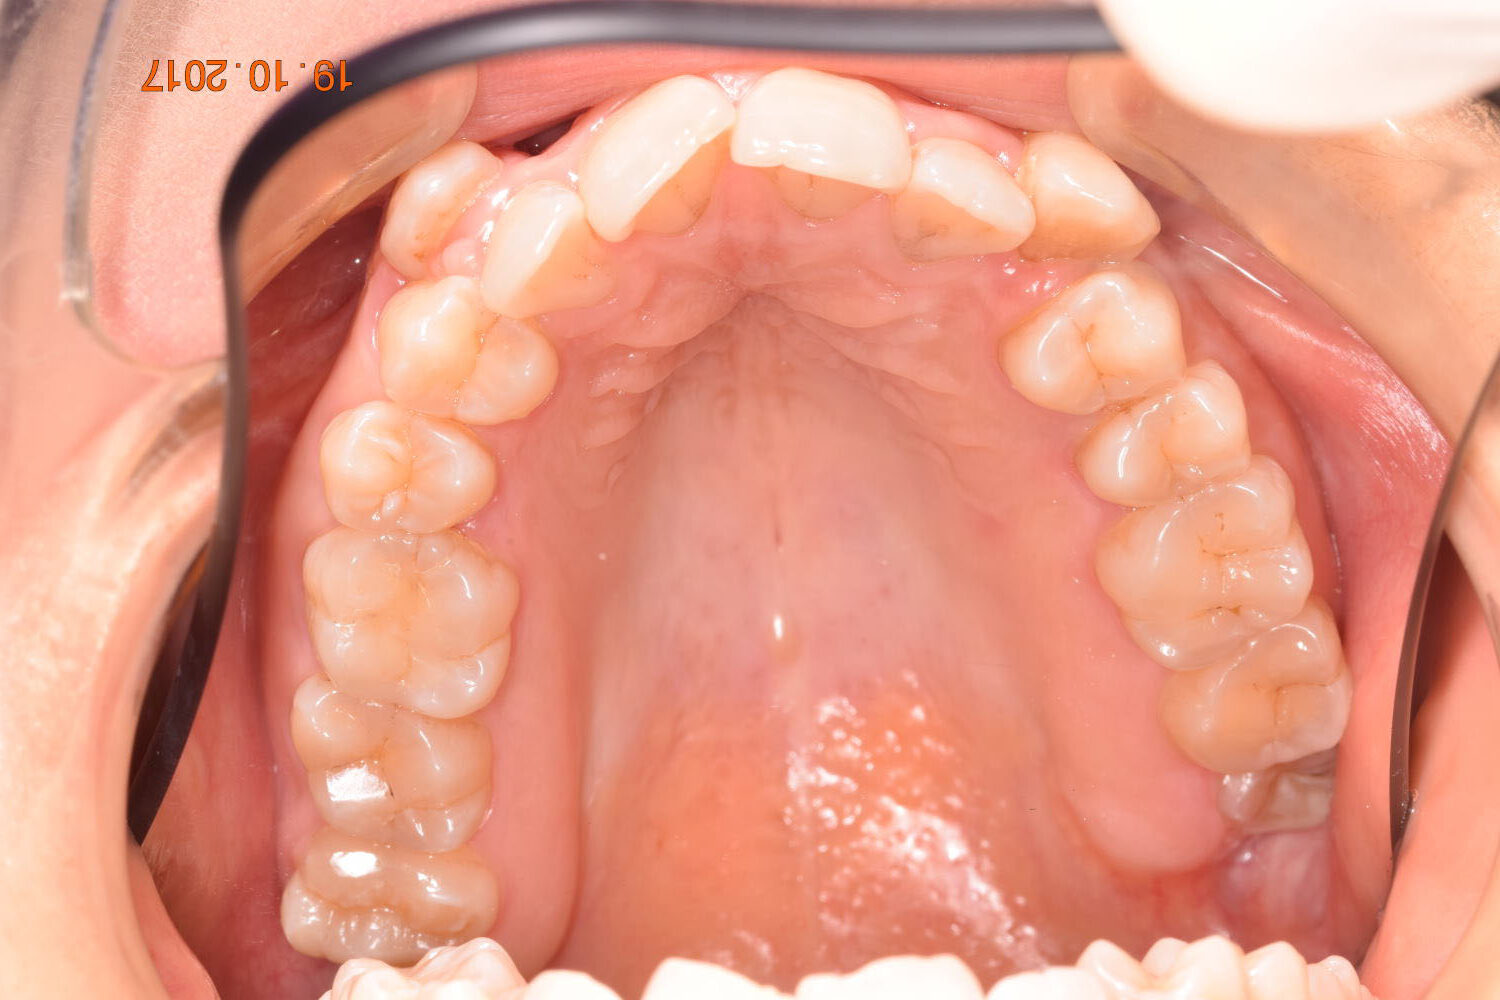

A 27-year-old female patient presented with class III malocclusion, 15 mm crowding in the upper arch, an anterior open bite, a lateral crossbite, and a total ABO score of 29. Her facial profile was straight with a retrusive maxilla, and the upper and lower incisors were retroclined. An extreme lack of midface support was also noted, and the constricted dental arches resulted in a poor smile width and dark buccal corridors. No myofunctional investigations were performed at the time, as they were initially considered unnecessary.

Adhering to the principles of Face First Orthodontics, the primary objective was to increase midface support by expanding the upper maxilla, fixing the cross bite, and aligning the teeth. Closing the open bite was a secondary objective.

The treatment began in 2017. Given the patient’s preference for less visible brackets, Damon Clear brackets were selected. High torque upper cuspids and low torque upper incisors were chosen to offer the best torque control for upper arch development. For the lower arch, there were no alternative bracket configurations available. Bite turbos were applied to the upper second molars.